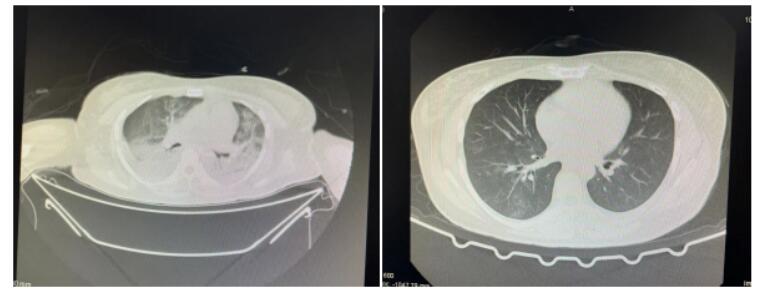

在CT影像显示下,正常人的肺部是呈现黑色影像,而重症肺炎患者双肺有大量渗出物,累及多个肺叶,影像学检查呈现出大范围的白色影像,也就是大家常说的“白肺”,其临床表现主要为胸闷气短、呼吸不畅,血氧饱和度较低等,是重症肺炎中死亡率很高的疾病。“送到医院来的时候,王女士双肺影像显示80%都已经白化。”刘建雄说。

1月5日,王女士复查CT显示“白肺”明显吸收,各项生命指标稳定,成功治愈出院。